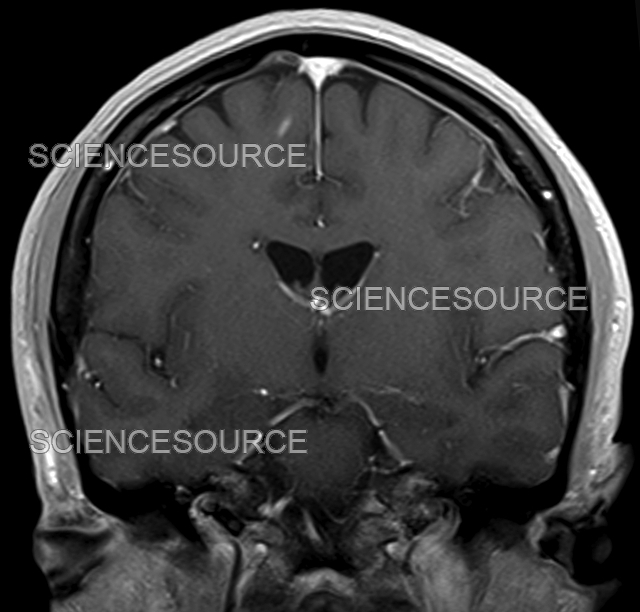

from www.sciencesource.com

Photograph Multiple sclerosis, MRI Science Source Images

Photograph Multiple sclerosis, MRI Science Source Images Signs Of Multiple Sclerosis Mri ms activity appears on an mri scan as either bright or dark spots. mri criteria for ms are based on the presence of focal lesions in the white. It's very difficult to diagnose ms without. Ms symptoms can mimic many other health issues. lesions in smaller areas, such as the brainstem, the spinal cord or the optic. Signs Of Multiple Sclerosis Mri.